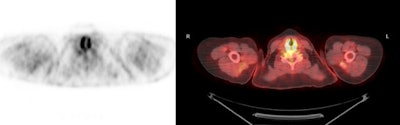

|

Benign adrenal lesion with FDG uptake: The patient shown below had a left adrenal mass which had remained stable for 2 years (white arrow). The stability over time and CT features would be consistent with a benign adrenal lesion- likely an adenoma. Note the marked FDG uptake within the mass on PET imaging (black arrows). Benign adrenal adenomas can accumulate FDG resulting in false positive exams. The use of PET/CT has been shown to improve the specificity of the PET exam. |

|

|